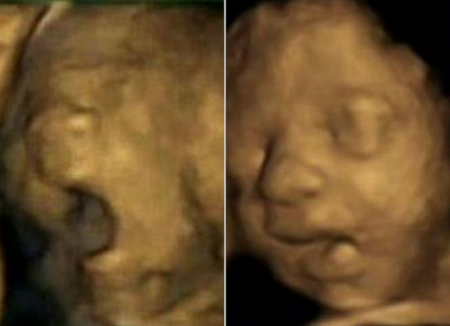

Hasta el momento no se había reparado en el comportamiento del bebé dentro del útero cuando la madre tiene signos de estrés, por eso un equipo de investigadores de las universidades de Durham y Lancaster han decidido estudiarlo y han publicado imágenes de ecografías en 4D para enseñarnos cómo son los gestos del bebé dentro del vientre de una madre estresada.

Los científicos han observado que los bebés de madres estresadas tienden a tocarse la cara más a menudo con su mano izquierda. Cuanto más estrés, más se tocaban los bebés la cara con esa mano.

También han visto que los bebés de madres que sufrían estrés bostezaban abriendo más la boca que los bebés de madres que no lo sufrían, aunque no sabemos exactamente qué les sugiere este hallazgo.